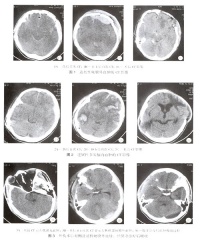

多发脑挫裂伤

双颞叶脑挫裂伤

对脑挫裂伤与脑震荡可以作出明确的鉴别诊断,并能清楚地显示脑挫裂伤的部位、程度和有无继发损害,如出血和水肿情况。同时,可根据脑室和脑池的大小、形态和移位的情况间接估计颅内压的高低。尤为重要的是,对一些不典型的病例,可以通过定期CT扫描,动态地观察脑水肿的演变或迟发性血肿的发生。近年来,在有此设备的医院CT已作为急性头伤的常规检查,因为单靠伤史和查体难以作出超早期诊断。Stein等(1990)指出在GCS13~15危害较小的轻型头

右额颞叶脑挫裂伤合并蛛网膜出血

伤中,首次CT的阳性发现率竟占18%,并有5%需行手术治疗,强调早期CT检查的必要性。